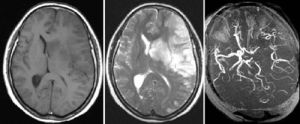

心電圖等可診斷腦梗塞1、CT和MRI檢查

可顯示缺血性梗死或出血性梗死改變,合併出血性梗死高度支持腦栓塞,許多患者繼發出血性梗死臨床症狀並加重,發病3~5日內複查CT可早期發現激發梗死後出血,及時調整治療方案,MRA可發現頸動脈狹窄程度或閉塞。

腦梗塞2、MRI檢查:MRI對腦梗死的檢出極為敏感,對腦部缺血性損害的檢出優於CT,能夠檢出較早期的腦缺血性損害,可在缺血1小時內見到。起病6小時後大梗死幾乎都能被MRI顯示,表現為T1加權低信號,T2加權高信號。

4、特殊檢查:經顱都卜勒超聲(TCD)、頸動脈彩色B超、磁共振、血管造影(MRA),數字減影全腦血管造影(DSA)、頸動脈造影,可明確有無顱內外動脈狹窄或閉塞。